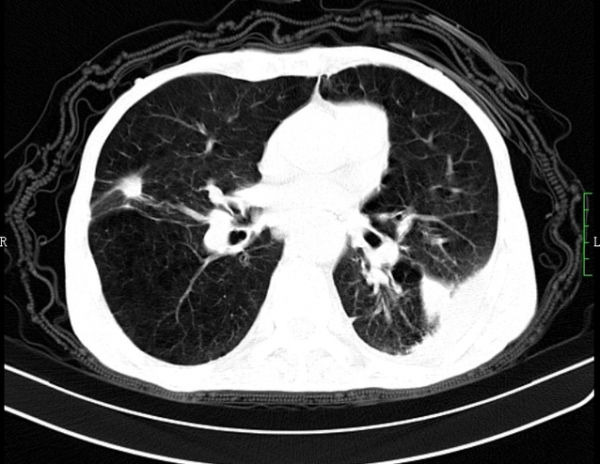

國慶前幾天接診了一個病人,54歲的徐先生睡眠不好已經持續半年左右了,剛開始在鎮上做了個全身體檢,醫生說肺裡有部分陰影建議徐先生去大醫院具體檢查一下,徐先生就做了個詳細的肺部CT,報告顯示雙肺紋理清晰,右肺中葉可見一高密度影,大小約為4mm,邊界清晰且血管行走自然,周圍也沒有腫大淋巴結的情況,所以主治醫生建議徐先生半年左右隨訪一次即可,儘管這樣徐先生還是不放心,畢竟自己還有甲狀腺結節的病史就找到了我。